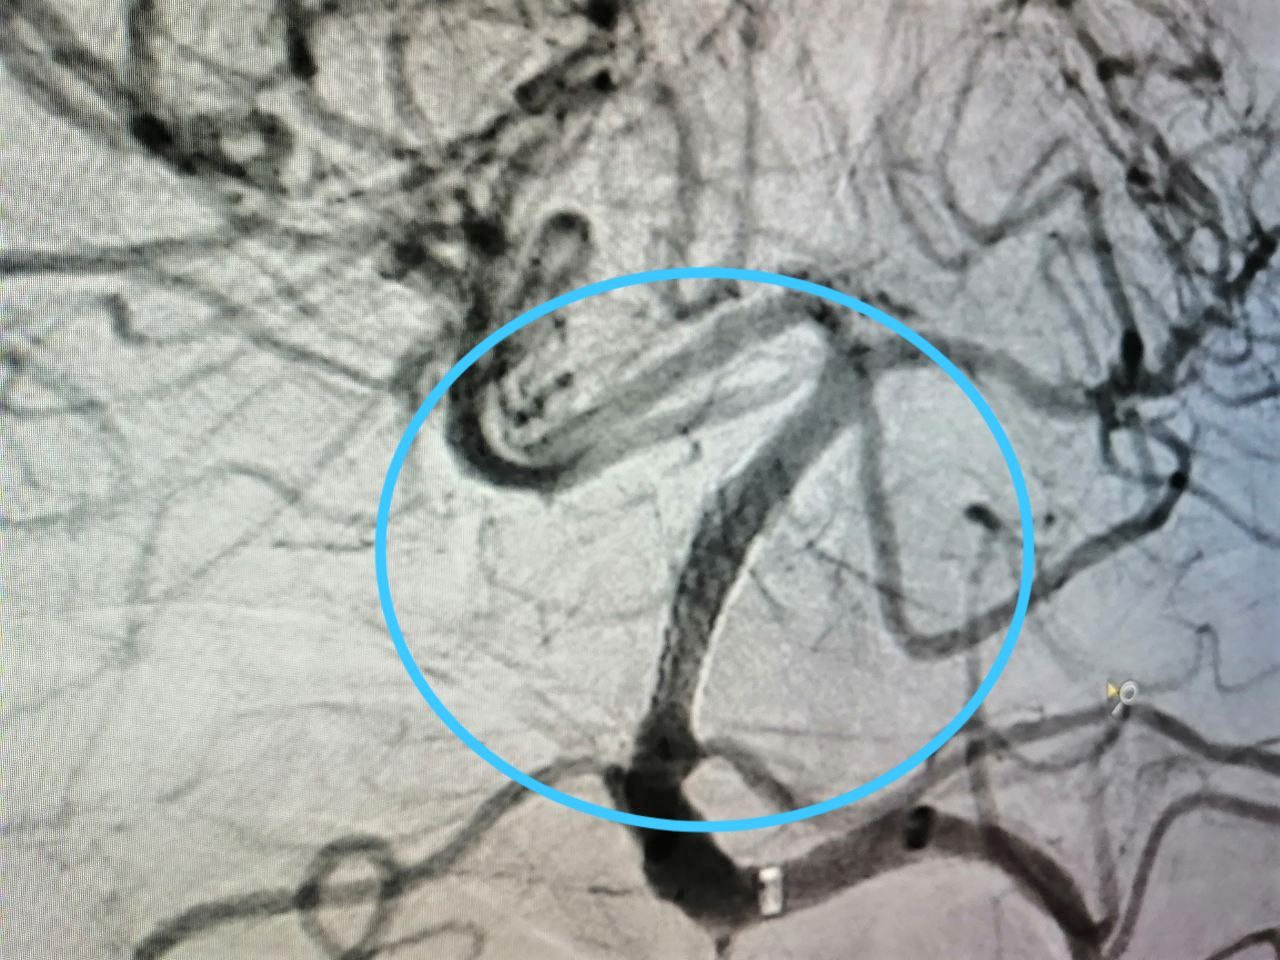

Поэтому следующим этапом оперативного лечения стала ангиопластика. Для неё используется баллонный катетер. Он вводится в сосуд и расширяется под давлением, устраняя стеноз. Как правило, такой «продувки» достаточно для восстановления сосуда в диаметре. Но в данном случае это помогло ненадолго – стенки артерии снова спадались, возвращаясь в прежнее положение. Тогда Максим Бессмертных принял решение об интракраниальном стентировании. Эта операция – из разряда крайних мер. Стентирования внутричерепных артерий при их сужении стараются избегать до последнего из-за высоких рисков.

-В отличие от сосудов сердца, сосуды головы менее прочные, их легче повредить при установке стента. Поэтому вмешательство является опасным и очень редким. Например, в 2021 году, по данным главного рентгенохирурга страны Баграта Алекяна, в России выполнено всего 55 таких операций, а количество стентирований коронарных артерий превысило 328 тысяч. В Сургутской травмбольнице за прошлый год проведено всего два интракраниальных стентирования. И в обоих случаях это был единственный шанс спасти человеку жизнь и дееспособность, – отмечает Максим Бессмертных.